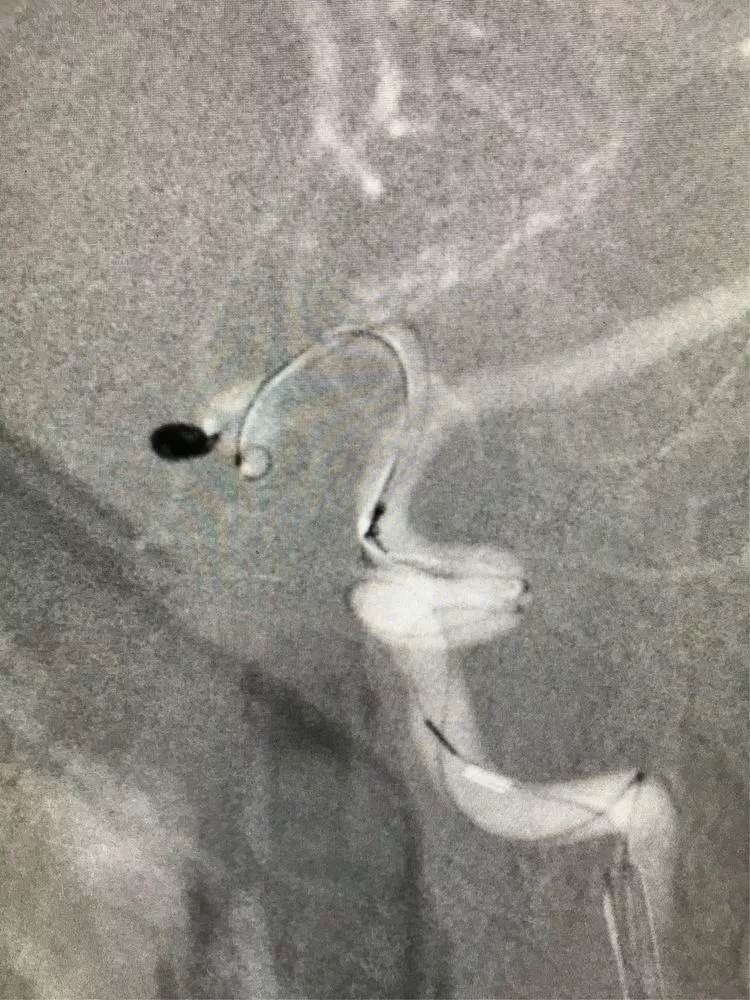

2根微导管进入2个子瘤,1号子瘤内弹簧圈能稳定填入,2号子瘤内弹簧圈不能稳定填入。

先把1号子瘤填瓷实。

再把1号微导管退到主瘤内,部分填入弹簧圈挡住2号子瘤的开口。

在弹簧圈的辅助下,对2号子瘤进行填塞。

继续2号子瘤的填塞(还是主瘤内弹簧圈辅助,填完后我想看看效果,就把辅助的弹簧圈又回收了。)

开始填主瘤。

换了一个角度进行填塞,主要是观察前交通的部位,避免弹簧圈影响到前交通。第一个成篮圈最为关键,既要避免分隔,又要保证不影响前交通。

然后双导管交替填塞,小心啊!每填完一个弹簧圈都造影看双侧大脑前A2的血流通畅情况。